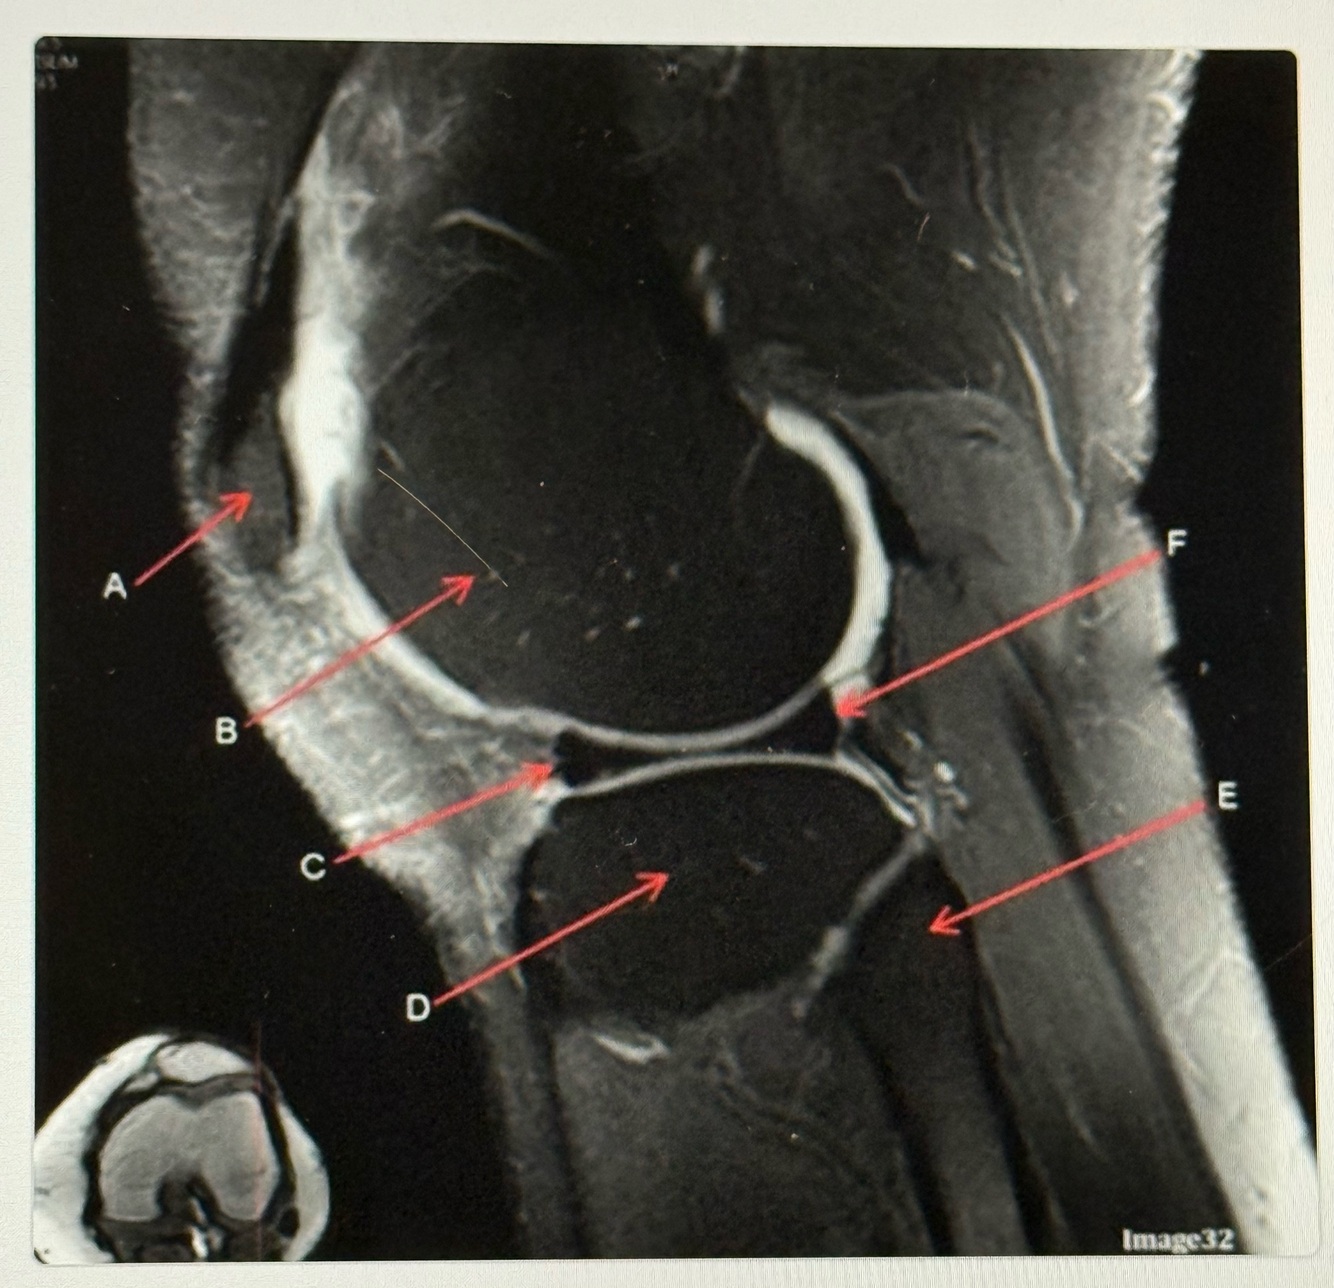

12

Q

Letter C points to the

A

Anterior horn of lateral meniscus

13

Letter D points to the

Tibia

14

Letter E points to the

Head of the fibula

15

Letter F points to the

Posterior horn of the lateral meniscus